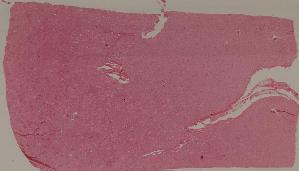

49.梅毒性主动脉炎

50.大叶性肺炎

51.肺肉质变

52.小叶性肺炎

57.肺癌

59.慢性萎缩性胃炎

60.胃溃疡

61.胃腺癌(胃粘液腺癌)

62.急性普通型病毒性肝炎

63.慢性活动性肝炎

64.急性重型病毒性肝炎

65.亚急性重型病毒性肝炎

66.活动性结节性肝硬化

67.非活动性结节性肝硬化

68.胆汁性肝硬化

69.肝细胞性肝癌

72.膜性肾小球肾炎

73.急性肾小球肾炎

74.新月体性肾炎

75.慢性硬化性肾小球肾炎